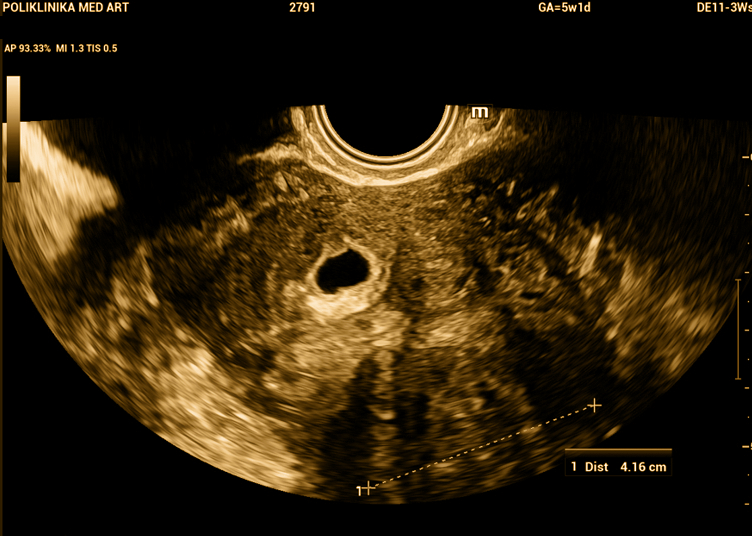

Miom i trudnoća. Gore desno u maternici se vidi gestacijska vrećica, a dolje lijevo je subserozni miom promjera 41 mm.

U trudnoći može doći do većeg porasta mioma te bolova u području maternice zbog propadanja mioma.

Većina trudnoća s miomima protekne uredno, bez ikakvih tegoba.

Važno je redovito praćenje mioma tijekom trudnoće. Nakon porođaja se miomi često smanje.